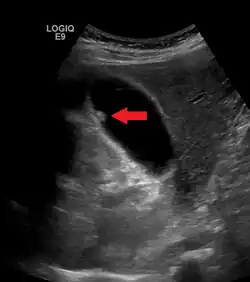

La mayoría de los PVB se diagnostican durante una ecografía abdominal. Si bien la ecografía abdominal es considerada el primer estudio para el diagnóstico, no es definitiva en relación con la presencia de un pólipo o su potencial maligno (5). Es difícil obtener una muestra histológica del pólipo. El uso de US abdominal, ultrasonido endoscópico (EUS), Tomografía axial computarizada (TAC), y tomografía por emisión de positrones más tomografía computada (PET/CT) con 18-fluorodeoxiglucosa (18-FDG) ayuda a predecir con mayor certeza la etiología de la lesión polipoide1,4.